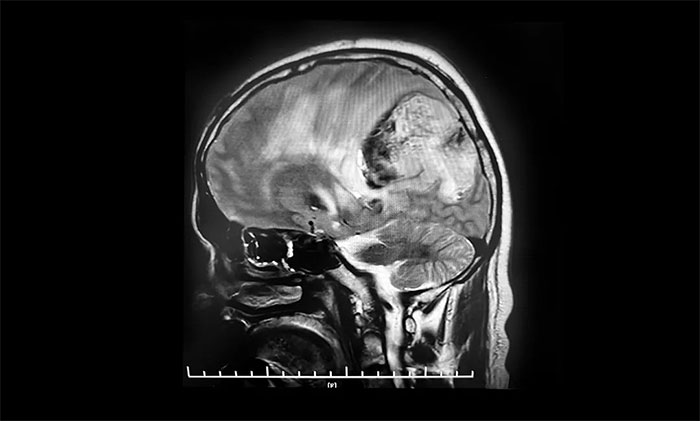

今年10月7日,患者突发意识不清,伴右手不自主抖动,呼唤有反应,反应迟钝,立即就诊于当地医院。行头颅增强MR提示:左侧额顶叶、胼胝体体部及压部、丘脑占位伴左侧顶叶占位,范围较前明显增大,均以弥漫性胶质瘤考虑伴左顶叶肿瘤卒中出血。10月11日,患者症状较前加重,出现嗜睡,反应迟钝,右侧肢体肌力明显下降。当地医院表示无法救治,希望渺茫。

头颅MRI平扫+增强+DWI+MRA提示,左侧顶枕叶巨大肿瘤伴局部瘤卒中,幕上脑室系统、脑干受压变形,中线结构右移19mm,大脑镰下疝形成。李士其教授等专家团队会诊指出,患者脑内巨大占位,性质不明,并且患者已经发生脑疝昏迷,生命危在旦夕,应尽快进行手术治疗,挽救患者生命,同时明确病理诊断。

▲ 左侧顶枕叶巨大肿瘤伴局部瘤卒中